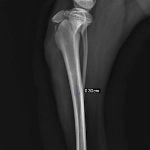

症例3:キルシュナーワイヤーのピンニングによる整復

ペルシャ猫 11ヶ月齢 雄

他院にて左大腿骨遠位の成長板骨折(salter-harrisⅠ型)が認められており、治療相談を目的として来院。当院にて、キルシュナーワイヤーを用いたピンニングにより骨折部位の整復を行いました。術後の経過は良好で、現在も経過観察中です。

術前レントゲン

術後レントゲン